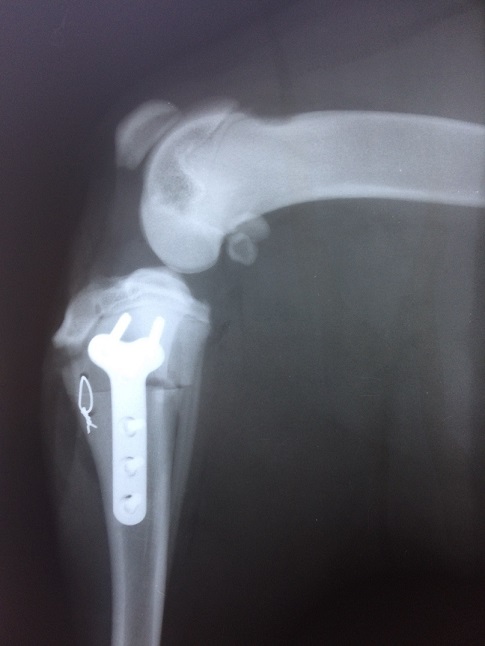

Добрый вечер форумчане. Гека мы потеряли в ноябре 2017 ... Это была тяжелейшая утрата... Решили сразу взять щенка, выбор пал на ротвейлера. И у нас снова беда... Да не совсем по теме форума-дисплазия, несформировавшиеся связки в 6 месяцев произошел обрыв связки. Вообщем начну сначала: взяли щенка, ему было около 3 месяцев, в 3 месяца идем к вету планово он замечает небольшую хромоту задней левой лапы, гелабон, витамины, чешский корм фитмин, все сбалансированно. В 6 месяцев на прогулке заваливается на лапу и не можем дальше идти... Рентген показывает дисплазию второй степени, едем в край в другую клинику там делаем операцию, запиливают кость под углом ставит титановую пластину,связок нет, на второй лапе такая же проблема... с передними лапами тоже проблема неравномерно развиваются кости, так вот вопрос вроде бы как дисплазия это генетика, опять генетика как и эпи... Звонил заводчикам те нахамили еще и угрожать начали) Каким образом можно повлиять на заводчиков? Куда обращаться? Здесь не столько стоит возврат денег, а беспредел разведенцев, ведь кто то усыпит такую собака или выгонит, как же так можно безответственно заниматься племенной работой...

В ставрополе делали операцию, док кандидат вет наук, оставил о себе очень положительное впечатление! да под наркозом снимки делали, 2 степень ставит дисплазии, но это полбеды связки их практически нет...

а это поле операции